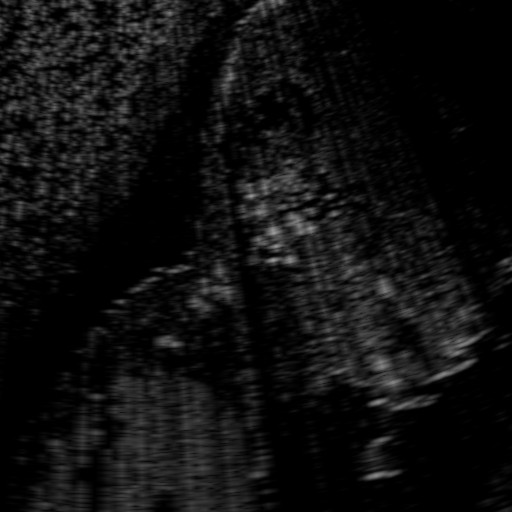

Above image translation has been demonstrated on patches. For the entire field-of-view (FoV) US images, patch fusion from image translation of non-overlapping patches would cause artifacts at image seams. Averaging overlapping patches, on the other hand, would blur the essential US texture. Although seamless tiling of US images is possible using graphical models [3], this requires prohibitively long computation time. Herein, we instead directly apply our trained generator on full FoV low-quality images, since the generator is fully convolutional and thus can operate on images of arbitrary size. Fig. 4 shows two examples of translated images by L2HMS and L2HMSA, demonstrating direct inference on full FoV images. While anatomical structures are well preserved and the effect of attenuation integral map is apparent, speckle texture appearance is seen to degrade slightly especially in the top image regions, where the ultrasound texture looking particularly different due to focusing difference and near-field effects.

(a) Input

(b) L2HM

(c) L2HMS

(d) L2HMSA

(e) Target